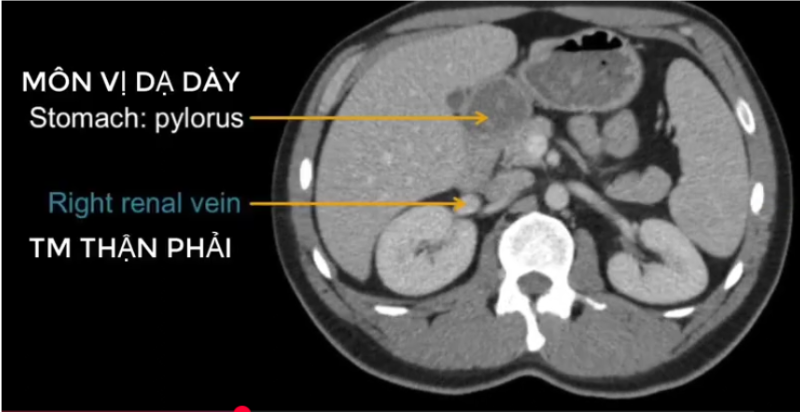

cq trong hình ?